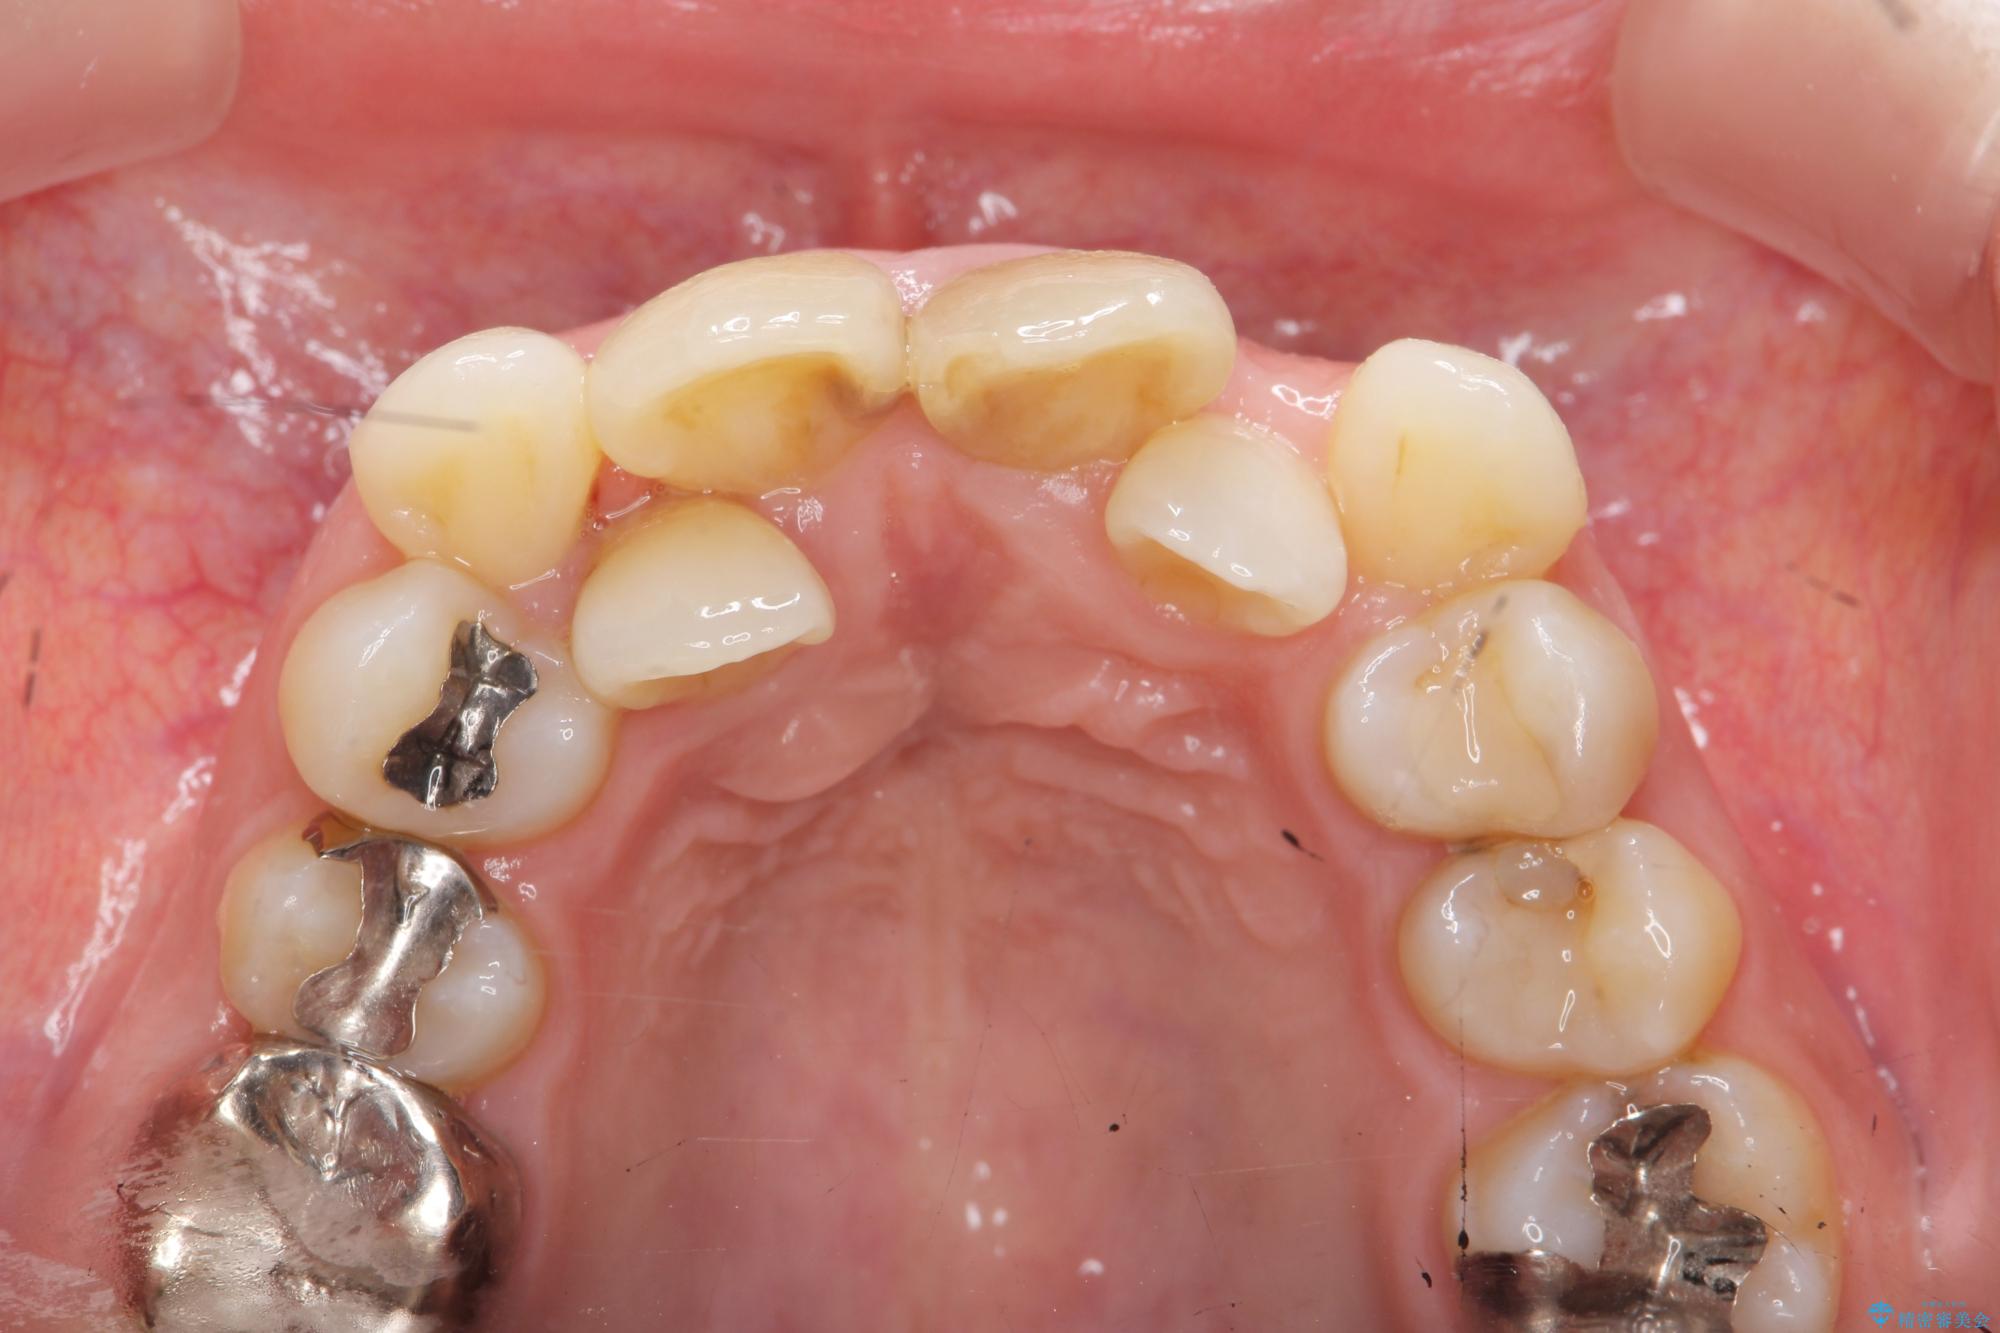

前歯の変色が気になるとご来院された患者様です。

レントゲン検査の結果、以前の根管治療の詰め物が突き出た状態でしたので、まず精密な再治療を行います。同時に、歯磨きがしにくく虫歯の原因になっている右上側切歯を抜歯し、その後、セラミック治療で全体を美しく修復する計画です。